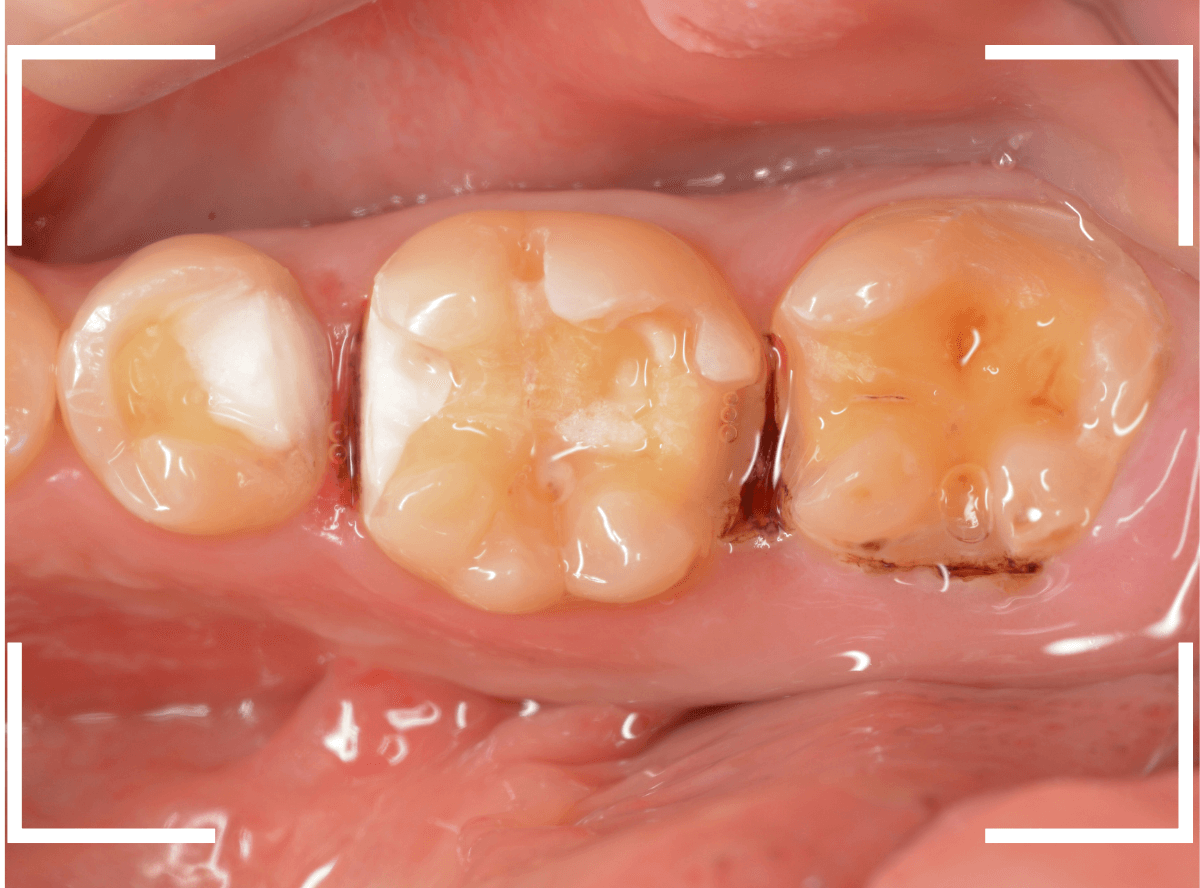

実際に使っている場面です。

虫歯の治療のブログでも紹介した症例ですが、レントゲン写真で、破折したレジンの中で神経の近くまで虫歯になっているのがわかります。

神経に近い虫歯ですので、いつも以上に慎重に虫歯をある程度除去したところで、虫歯の状況を検知液で確認します。

薄く赤く染まっているところが虫歯です。

逆に、他の色がついているところは、虫歯ではないので、削らなくてもよいという事ですね。